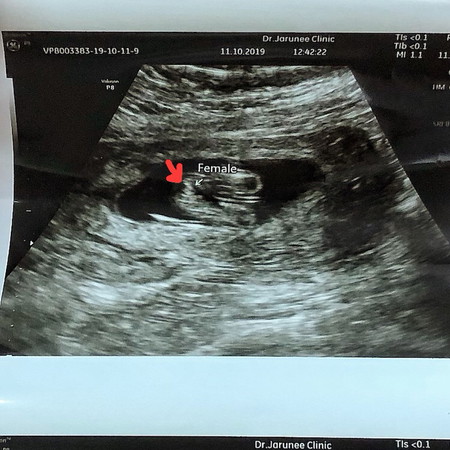

แม่บ้านใหนมีภาพอัลตร้าซาวเพศลูกชัดๆไหมค่ะ พึ่งไปซาวมา 15w หมอบอกว่าน่าจะผญ มองดูก็เหมือนน่ะค่ะ แต่ทำใมเหมือนมีกลีบ2อัน เห็นเหมือนกันไหมค่ะ

ช่วยดูหน่อยคะแม่ๆ ไปซาวมาหมอบอกยังไม่รู้เพศเลบคะ มีแม่ๆบ้านไหนเห็นเพศของหนูแล้วบ้างคะ 💕

ดูแล้วก็เห็นเป็นเป็นกลีบ ก็น่าจะผู้หญิงน่ะแม่ ของบ้านนี้ผู้ชายจู๋โผล่ ชัดมาก

ปกติใช่มั้ยค่ะ เห็นเป็นกลีบ ก็ว่าผญแน่ๆ

เป็นกลีบก็ถูกแล้วนิคะ ผู้หญิงต้องมีกลีบ

บ้านนี้หมอก็บอกว่าผู้หญิงค่ะ